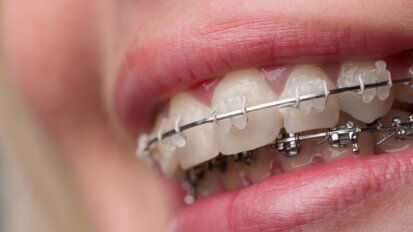

Wpływ czynników estetycznych na wybór metody rehabilitacji implantoprotetycznej

Autorzy pracy przedstawiają 4 przypadki rekonstrukcji implantoprotetycznych, różniące się między sobą stopniem trudności, rodzajem ...